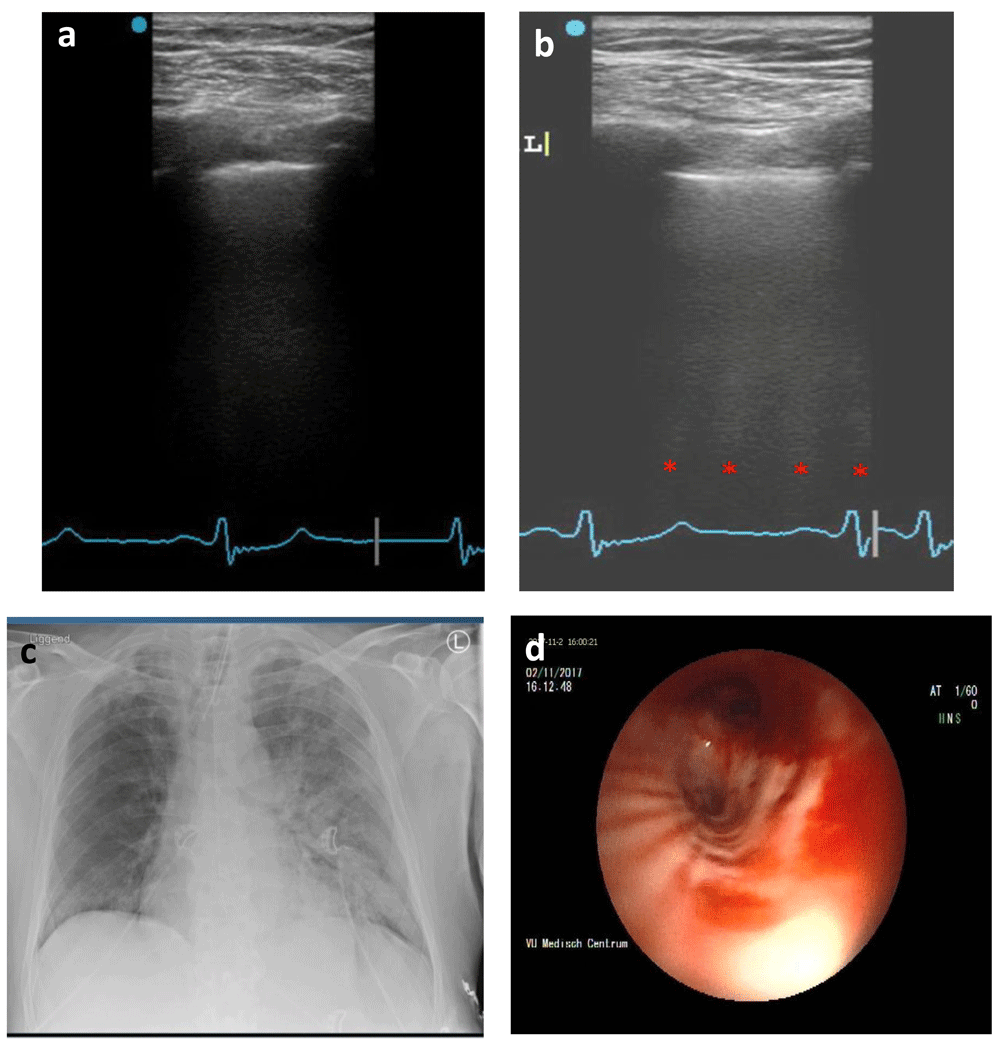

A 65-year old Caucasian male presented to the emergency ward with hemoptysis and respiratory distress. The patient’s history contained multiple pulmonary embolisms and subsequent chronic thromboembolic pulmonary hypertension, for which he was using acenocoumarol. Additionally, a non-specified form of pulmonary vasculitis was suspected, with concomitant treatment of prednisone. Bronchoscopy revealed pulmonary hemorrhage originating from the right pulmonary artery, which was coiled, and ICU admission followed. Two days after admission the patient was stable and extubated but showed signs of respiratory distress within the same day. Non-invasive ventilatory assistance failed and the patient was reintubated, while tranexamic acid (intravenous single dose, 1000 mg) was started as the cause was suspected to be a rebleed. Ultrasound examination according to the BLUE-protocol showed an A/B-profile (Figure 1a, b) and chest X-ray showed left-sided consolidation (Figure 1c). Subsequent bronchoscopy revealed a bleed originating from the left upper lobe (Figure 1d) which was successfully coiled.

(a) A-profile (right lung). (b) B-profile with four distinguishable B-lines (left lung). Red dots, B-lines. (c) Chest X-ray with marked consolidation in the left lung. (d) Bronchoscopy of left main bronchus displaying bleeding from the upper lobe.